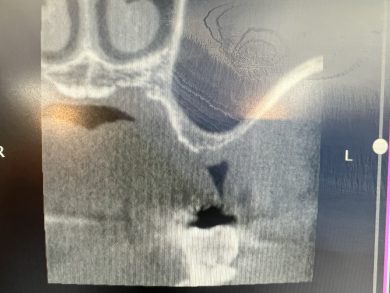

患者さんは75歳の男性。歯性上顎洞炎で公立病院で左上奥歯を抜歯されました。上顎の骨が少なく、公立病院では「インプラントは難しい」と言われた方です。その後当院で義歯を製作しましたが、「やはり自分の歯のように咬みたい」という強いご希望がありました。

診査・診断を重ね、グラフトレスの設計で挑戦することを決断しました。

その名護先生に本日のレントゲンをお送りしたところ、

「ベスト。経験ある先生ほど臨床をシフトチェンジするのが難しいが、上原先生は見事にシフトチェンジされた」

とお返事をいただきました。